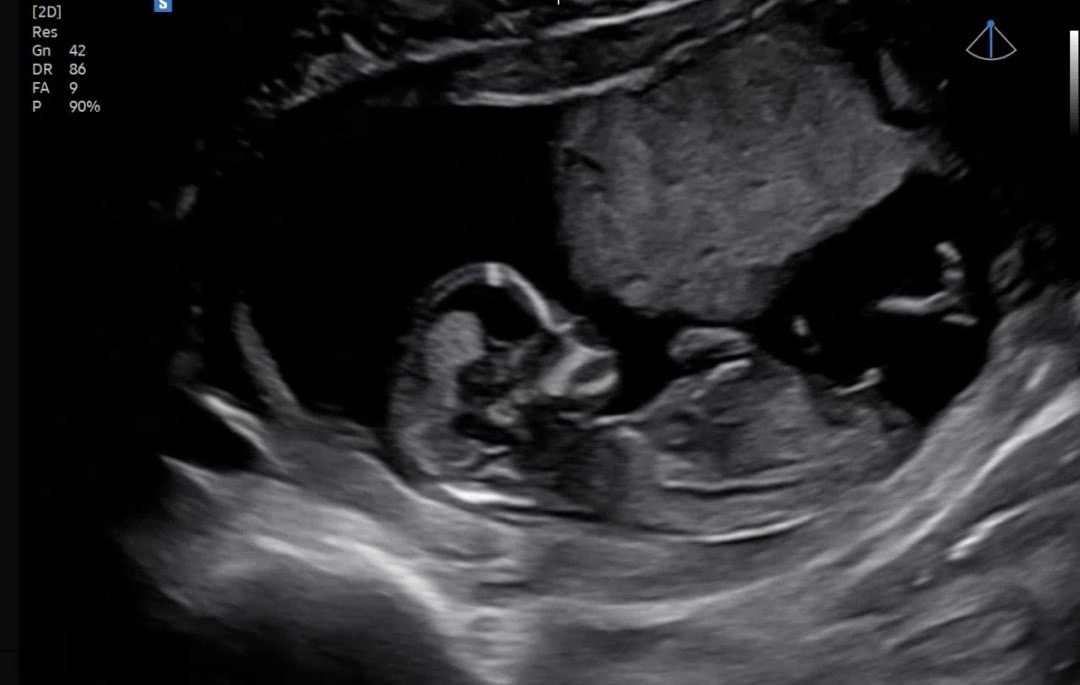

12주4일인데ㅠ 저는 봐도 모르겠어요! 고수님들 도와주세요~~

끝이 올라가서 아들같아욤!